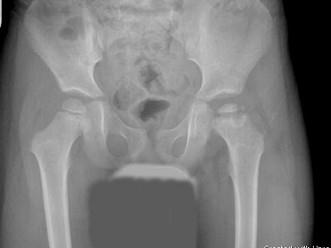

问题 男,5岁,髋疼痛乏力左腿跛行5个月,请结合图像,选出最可能的诊断 ( )

选项 A、骨囊肿 B、软骨肉瘤 C、骨肉瘤 D、股骨头骨骺缺血坏死 E、髋关节结核

答案 D